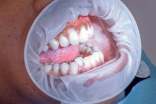

牙齦癌多為高分化的鱗狀細(xì)胞癌,以潰瘍型為最多見(jiàn)。下牙齦較上牙齦多發(fā),腫瘤生長(zhǎng)緩慢,男性多于女性,臨床可表現(xiàn)為潰瘍或乳頭狀突起。牙齦癌發(fā)病僅次于舌癌居第二位或第三位。占口腔癌的19.3%, 牙齦癌在唇癌、口腔癌中的比例呈逐年下降趨勢(shì), 已從最高32.06%下降至22.48%, 甚至20% 以?xún)?nèi)。

牙齦癌在臨床上可表現(xiàn)為潰瘍型或外生型,其中以潰瘍型為多見(jiàn)。起始多源于牙間乳頭及齦緣區(qū)。潰瘍呈表淺、淡紅,以后可出現(xiàn)增生。由于黏骨膜與牙槽突附麗甚緊,較易早期侵犯牙槽突骨膜及骨質(zhì),進(jìn)而出現(xiàn)牙松動(dòng),并可發(fā)生脫落。x線(xiàn)片可出現(xiàn)惡性腫瘤的破壞特征——蟲(chóng)蝕狀況部分規(guī)則吸收。

牙齦癌常發(fā)生繼發(fā)感染,腫瘤伴以壞死組織,觸之至出血。體積過(guò)大時(shí)可出現(xiàn)面部腫脹,侵潤(rùn)皮膚。牙齦癌侵犯骨質(zhì)后,常出現(xiàn)下頜下淋巴結(jié)轉(zhuǎn)移,后期則頸深上群淋巴結(jié)受累。